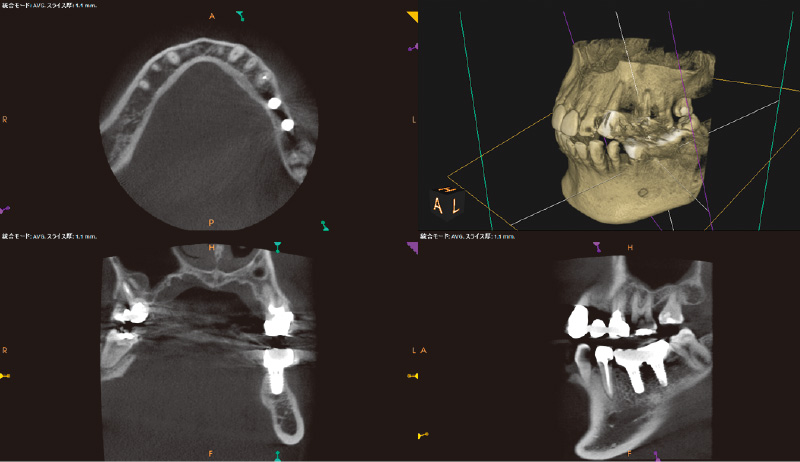

₆、₇にインプラントを埋入し左側の咬合を得る治療計画を立案。φ4.5長さ9.5mmのSPIイニセルインプラント エレメントRCを埋入した(図8)。まずはここで初期固定を得られたのでヒーリングキャップにて封鎖した(図9)。今回は勤務医たちへの指導の意味もあり、ガイデッドサージェリーにて行った。そして4週目でクローズドトレーにてシリコン印象を行い補綴装置をセットした(図10,11)。CBCT撮影を行い骨レベルの状態を確認し、機能的審美的にも問題ないことがわかっている(図12, 13)。

![[写真] 骨レベルの状態確認のためCBCT撮影](/academic/dentalmagazine/wp-content/uploads/sites/2/2025/09/194-8_photo12.jpg)

![[写真] 骨レベルの状態確認のためCBCT撮影](/academic/dentalmagazine/wp-content/uploads/sites/2/2025/09/194-8_photo13.jpg)